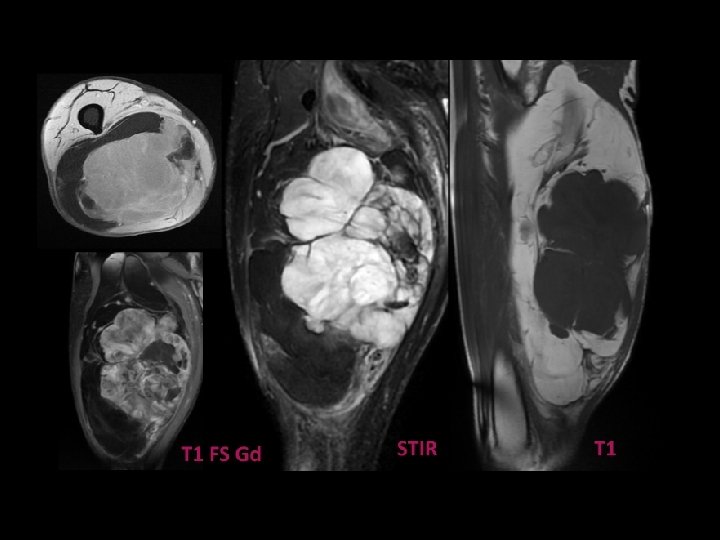

LIPOSARCOME BIEN DIFFERENCIE IRM: • Masse de signal graisseux - en hypersignal T 1 et T 2 - effacement du signal de la graisse • En faveur de la malignité: - septas épais > 2 mm - éléments nodulaires et tissulaires

Liposarcome bien différencié de l’épaule. IRM en coupe axiales en séquences pondérées T 1 (a) et T 1 fat-sat gado (b). Septa épais se rehaussant après injection de Gadolinium contrairement au reste de la tumeur graisseuse

Liposarcome bien différencié de la loge postérieure de la cuisse IRM en coupe axiale (a) et sagittale (b) en séquences pondérées T 1. Volumineuse tumeur de signal graisseux présentant des septa épais et des nodules tissulaires intratumoraux (têtes de flèches).

a Liposarcome bien différencié de la loge postérieure de la cuisse. IRM en coupe axiales en séquences pondérées T 1 (a) et T 1 fat-sat gadolinium (b) La présence d’un volumineux nodule tissulaire intra tumoral se rehaussant de façon important (flèches) est très en faveur de la malignité de la masse. b

Liposarcome bien différencié de la hanche Coupe axiale pondérée SE T 1 (a), frontale pondérée T 2 (b) et axiale pondérée SE T 1 avec Fat Sat et injection de Gadolinium (c): tumeur graisseuse avec des travées nombreuses et relativement épaisses